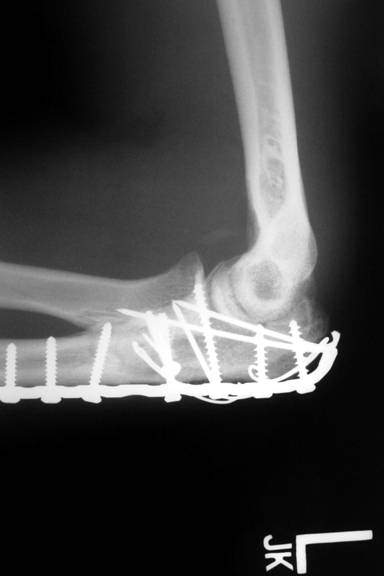

AC is a 25 year old male who was assaulted with a baseball bat. He sustained a shattered proximal ulna fracture with elbow dislocation. Surgery required application of a plate and screws, as well as pinning and cerclage wiring. He worked diligently in therapy to regain the excellent range of motion in his elbow as demonstrated in the photo with me.